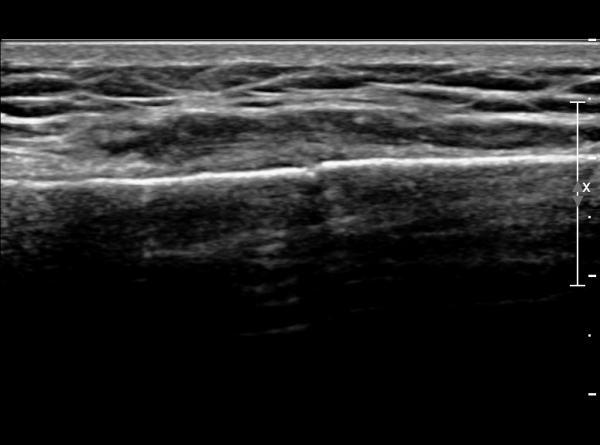

ÃÊÀ½ÆÄ °Ë»ç : ¼Õ¸ñ ¼ö±Ù°ü ±ÙÀ§ºÎ Ⱦ´Ü¸é°Ë»ç¿¡¼­ Äá¾Ë»À Ç¥ÃþÀ¸·Î ¾à°£ÀÇ ¿¬ºÎÁ¶Á÷ ºÎÁ¾ÀÌ °üÂûµÊ(»çÁø 1).